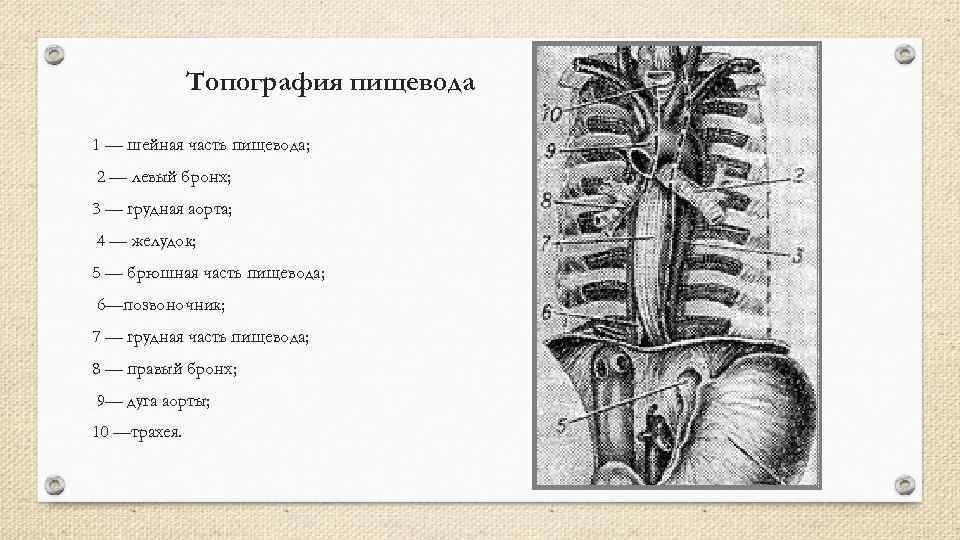

Топография пищевода 1 — шейная часть пищевода; 2 — левый бронх; 3 — грудная аорта; 4 — желудок; 5 — брюшная часть пищевода; 6—позвоночник; 7 — грудная часть пищевода; 8 — правый бронх; 9— дуга аорты; 10 —трахея.

Топография пищевода 1 — шейная часть пищевода; 2 — левый бронх; 3 — грудная аорта; 4 — желудок; 5 — брюшная часть пищевода; 6—позвоночник; 7 — грудная часть пищевода; 8 — правый бронх; 9— дуга аорты; 10 —трахея.